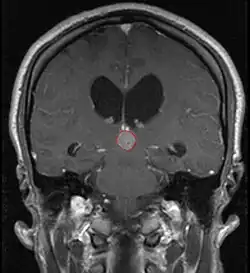

Radiation Oncology/CNS/Pineal

Pineal Gland Tumors

Pineal Gland Histology

• Principle cell in the pineal gland is the pinealocyte

• Germ cells are embryonal remnants, typically presenting in midline structures

Treatment Overview

• Work-up includes MRI, CSF, serum markers for bHCG and AFP

• Tissue diagnosis is critical, since management varies significantly based on pathology